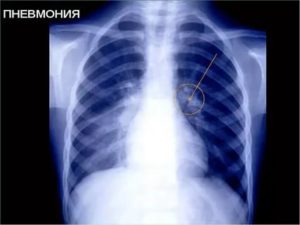

Чтобы найти ответ, как распознать пневмонию, предлагаем читателям ознакомиться с диагностическими алгоритмами, которые использует пульмонология для выявления заболевания. Они основаны на осмотре пациента, результатах клинико-диагностических методов исследования и лабораторных анализах.

Для выявления воспаления легких применяются следующие методы диагностики пневмонии:

Первоначально признаки воспалительных изменений в легочной ткани можно предположить на основе анализа клинической картины заболевания у пациента. Чтобы диагностировать патологию, необходимо выявить 2 из 4 нижеперечисленных признаков:

Для постановки диагноза недостаточно данных, которые получают при использовании физикальных методов исследования и внешнем осмотре. Медицинское обследование – обязательное условие, при несоблюдении которого нельзя определить точную причину недомогания. Полноценную диагностику можно провести только в стационаре при наличии необходимого оборудования.